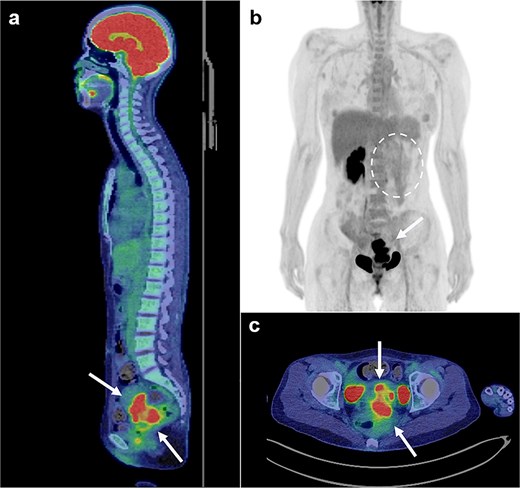

Magnetic resonance imaging revealed masses on the anterior uterine wall, as well as on the posterior uterine wall (Fig. 1a and b). Endometrial cysts were confirmed in the Douglas pouch (Fig. 1c and d). Computed tomography revealed left hydroureter and hydronephrosis, and no distant or lymph node metastases were observed. A Tc99m-diethylenetriaminepentaacetic acid renal renogram showed that the left kidney was nonfunctional. 18F-fluorodeoxyglucose (FDG)-positron emission tomography and computed tomography showed that abnormal FDG accumulation was observed only in the pelvis (Fig. 2). At first, no lesions were found on the uterine cervix or vaginal walls, and the cervical and endometrial cytology were negative. However, as time passed, the tumor emerged on the posterior vaginal fornix and was histologically diagnosed as high-grade endometrioid carcinoma (Fig. 3).

FDG positron emission tomography and computed tomography scans (FDG PET/CT). FDG PET/CT revealed that the mass that had FDG uptake solely in the pelvis (a, b, c: arrows). The left kidney did not uptake FDG because it was non-functioning (b: circle with dotted line).